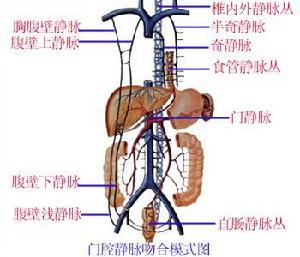

腹膜後間隙可按解剖部位簡易地分為五個區域:①腎周間隙;②上腹膜後間隙;③盆腔間隙;④下腹膜後聯和盆腔間隙;⑤局限性肌肉-骨骼間隙,以利分析影響後果的因素。

感染或膿腫一般局限在某原發部位,但可能向對側或由一個間隙向另一間隙播散。少數情況亦可沿筋膜平面或穿透膜向遠處擴散,如深部骨盆腹膜下;腸系膜根部;股、髖、前腹壁、背及脅皮下組織;膈下、縱膈及胸腔;甚至形成瀰漫性後腹膜感染,引起蜂窩組織炎並致壞死。